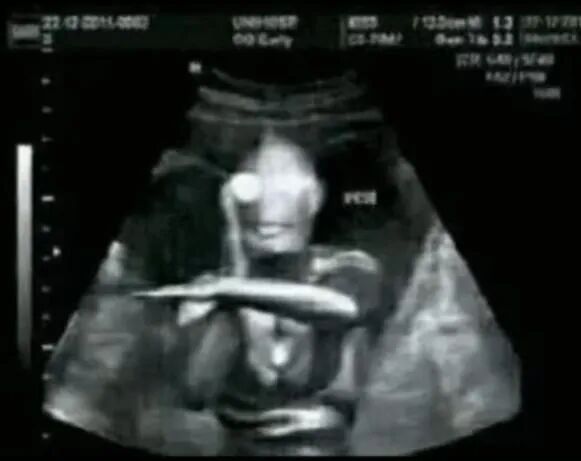

利用超声波来显示耳体结构或胚胎发育情况的诊断用的成像法,就叫ultrasonography(超声波检查法),“B超”就是超声波检查其中的一种。

它是以灰阶即亮度(brightness)模式形式来诊断疾病,取brightness首字母大写简写为B-scan ultrasonography。

所以,B超的“B”其实就是brightness。